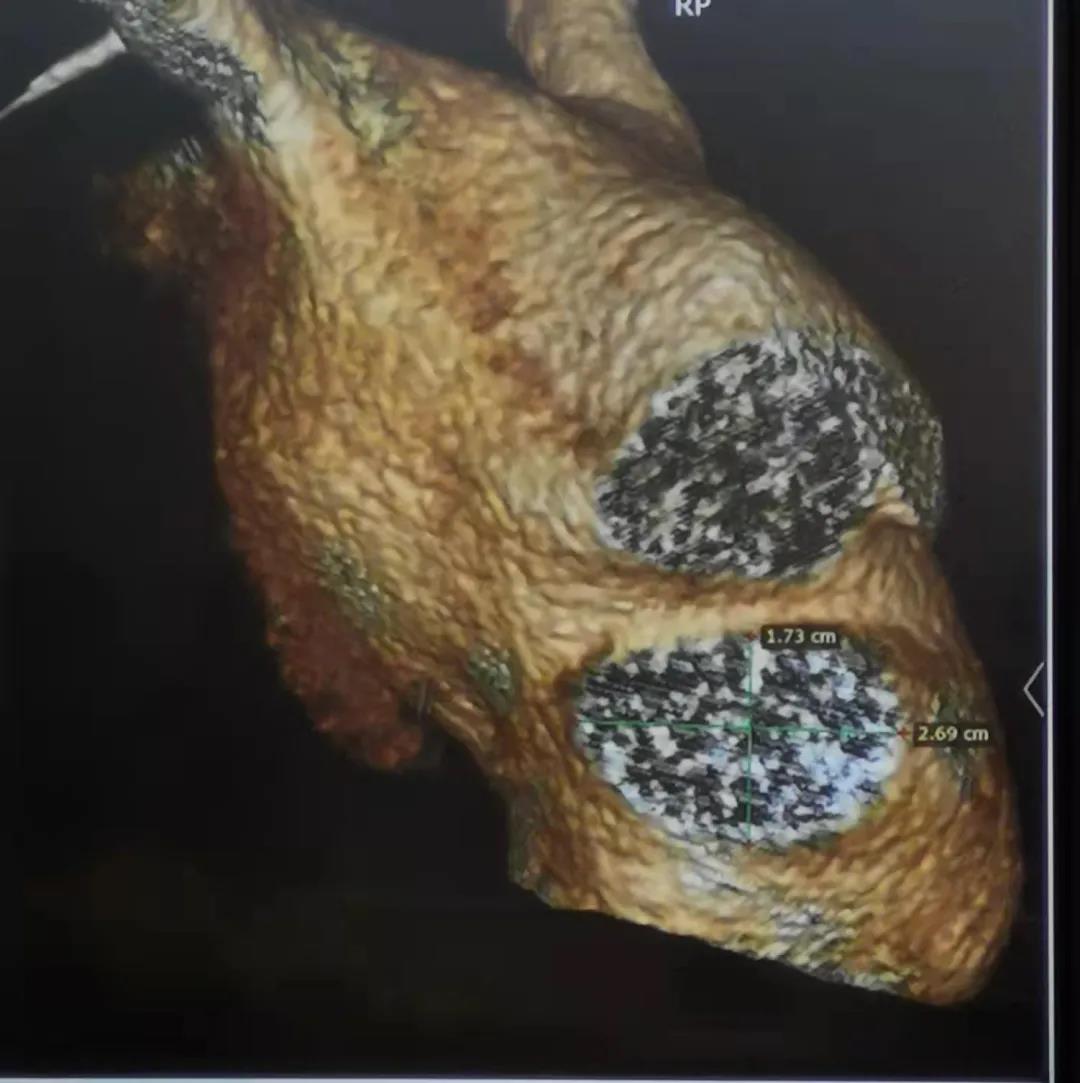

患者为66岁男性,患有持续性房颤、冠状动脉粥样硬化、高脂血症。术前CT三维沉建显示左心耳开口为17*27mm,选用LAmbre?2228封堵器进行封堵,多角度造影及TEE显示封堵成效梦想,无残存分流。LAmbre?更为轻微的输送鞘能够有效削减医源性危险的产生,患者术后复原优良。